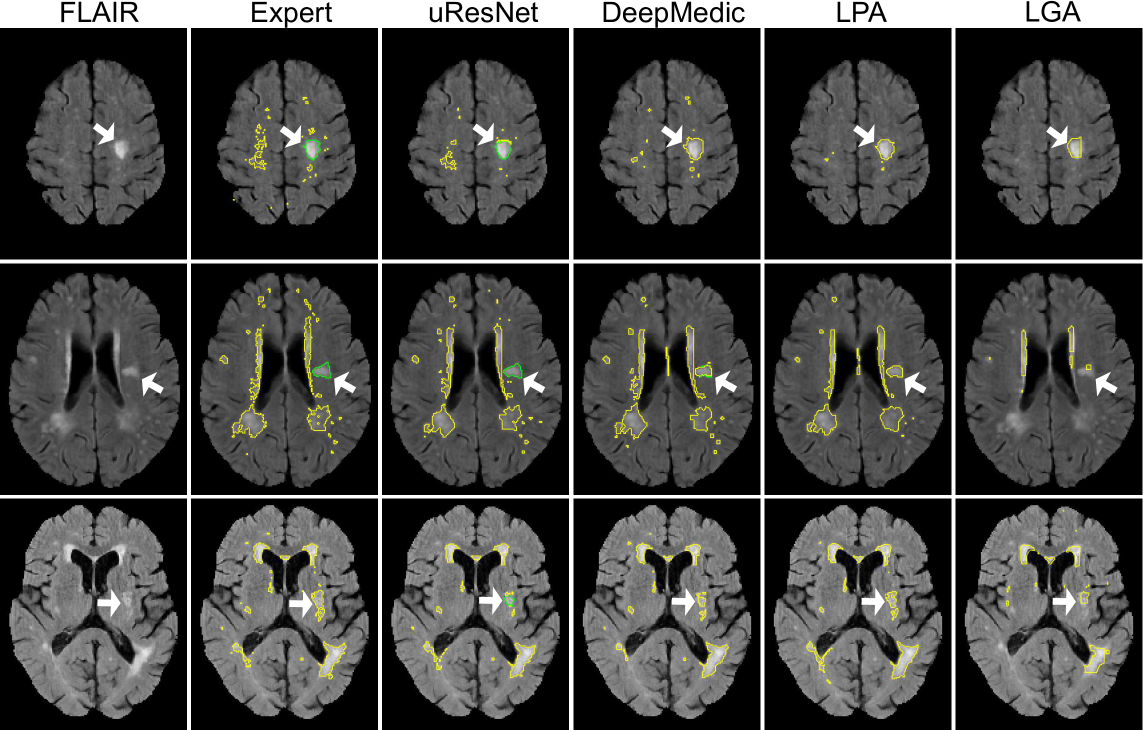

Figure 8 shows the segmentation results from three example subjects that illustrate the differences between the methods. Here, it can be observed that uResNet generally does a better job at differentiating between WMH and stroke lesions when compared to DeepMedic (top and middle row). In the bottom row of Figure 8 and example is illustrated when uResNet wrongly segments some WMH as stroke. Additionally, in the top row, all methods are shown to clearly under-segment the image when compared to the expert is shown. However, inspecting the FLAIR image of this subject (top row, leftmost column) it can be seen that the under-segmented regions would be challenging even for another expert annotator.

Figure 8: Visual comparisons of all competing methods. Yellow lines delineate WMH, green lines stroke and white arrows point to interesting result areas. Best seen in color.